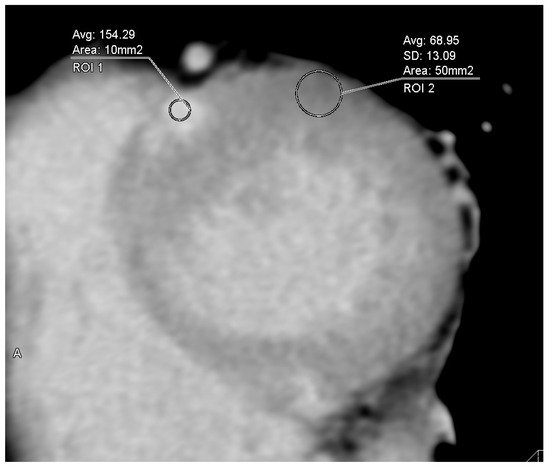

With the advancement of fractional flow reserve (FFR) derived from computed tomography (FFRCT), virtual stenting technology has gradually developed. This study investigated the performance of virtual stenting based on FFRCT in predicting post-percuta...